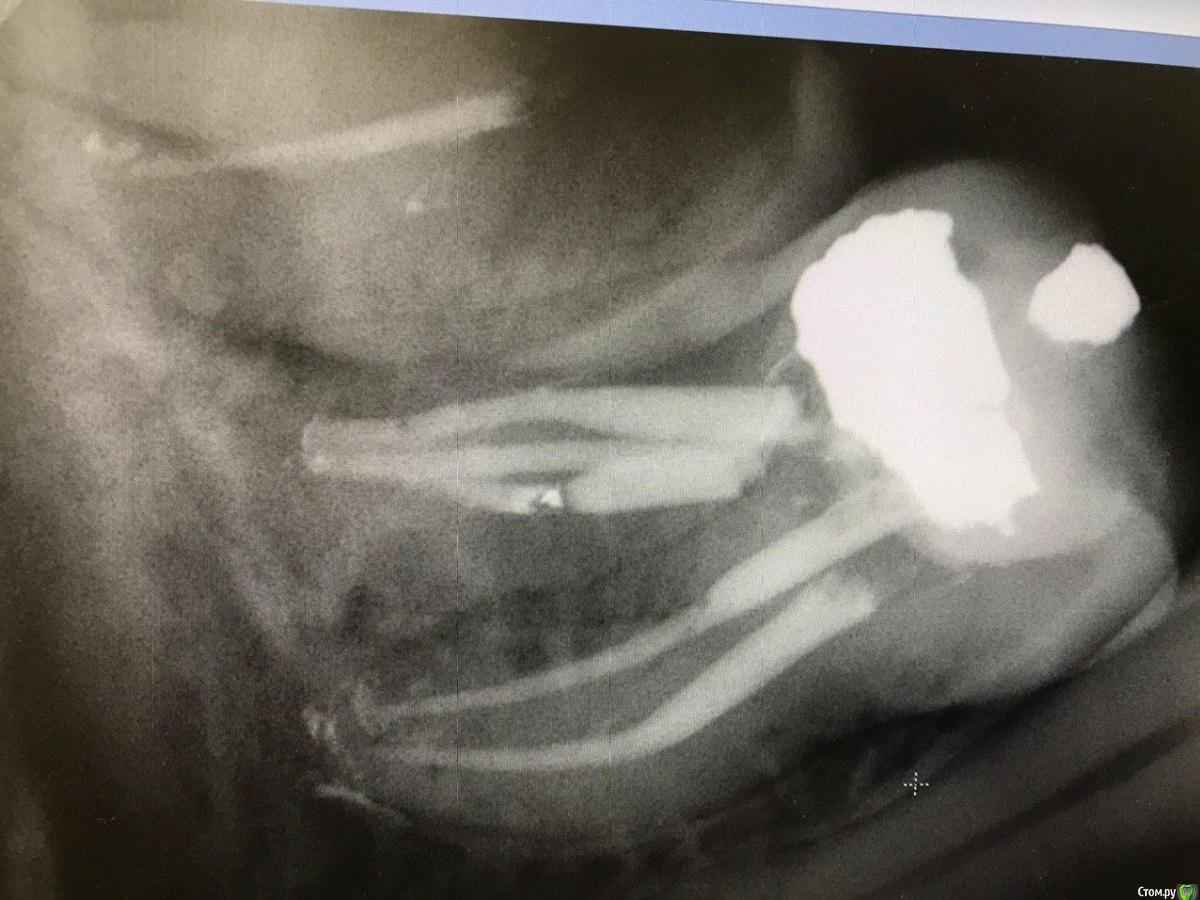

1586Doc Опубликовано 13 февраля, 2020 Автор Поделиться Опубликовано 13 февраля, 2020 вот с таким 46 работал на днях. У пациентки контрактура, очень сложный доступ. Обработка Xp shaper, пломбировка вертикальная конденсация. Понятно, что не идеально, но условия не позволили лучше 2 Ссылка на комментарий

annda Опубликовано 13 февраля, 2020 Поделиться Опубликовано 13 февраля, 2020 апексы не разбиваете? Ссылка на комментарий

1586Doc Опубликовано 13 февраля, 2020 Автор Поделиться Опубликовано 13 февраля, 2020 апексы не разбиваете? я аккуратен, и проверяю иногда ручными на этапе обработки. Сам инструмент достаточно гибкий. Единственный минус для меня, это его цена. Но время сейчас становится все дороже и уже на цену обращаешь меньше времени.Еще с апексом от мориты он не очень дружен, но тут возможно надо с настройками разобраться. (отключить авто реверс, замедление скорости при подходе к апексу) Ссылка на комментарий